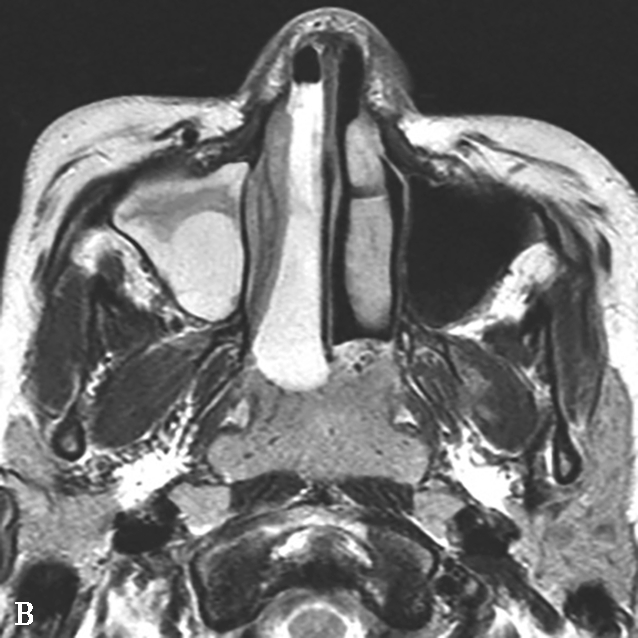

图1-3-26 鼻腔鼻窦肉芽肿性多血管炎

A、B.横断面CT及冠状面CT骨窗,示鼻背部塌陷,鼻中隔、双侧筛窦及上颌窦黏膜增厚,窦壁骨质增生硬化,内缘骨皮质欠光整;双侧中、下鼻甲形态欠自然,双侧眼眶内下壁骨皮质部分缺损,邻近内下象限肌锥外间隙可见弥漫性软组织增厚影,右侧为著;双侧上颌窦口-鼻道复合体增宽,钩突缺如;C.横断面T 1 WI,示双侧上颌窦腔可见略低信号,气-液平面可见,鼻背部塌陷,鼻中隔黏膜增厚,鼻咽顶后壁软组织增厚,呈等信号;D.横断面T 2 WI,示上颌窦腔病变呈高信号,余病变呈略低信号;E.横断面T 1 WI+FS+C,示窦腔、鼻中隔增厚,黏膜及其他受累结构呈中等强化,双侧翼腭窝及上颌窦后脂肪间隙受累,强化;F.冠状面T 1 WI+FS+C,示双侧眼眶内下象限肌锥外间隙病变呈中等强化,大脑纵裂及额部脑膜受累,呈弥漫性增厚强化